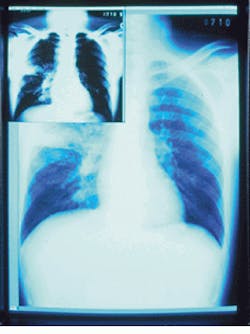

"By restricting the display to shades of gray, more accurate radiograms can be displayed. Radiographic display generally requires more than 256 shades of gray. Metheus` display controller, the P1540, can display more than 1000 shades of gray simultaneously." In addition, he says, "radiologists want to perform real-time windowing and leveling of 12-bit images on a 10-bit display at 70 Hz and `window to window copy` operations very quickly" (see Fig. 1).

FIGURE 1. Metheus` display controller, the P1540, can display multiple gray scales and provide windowing and leveling of 12-bit images to a 10-bit display.